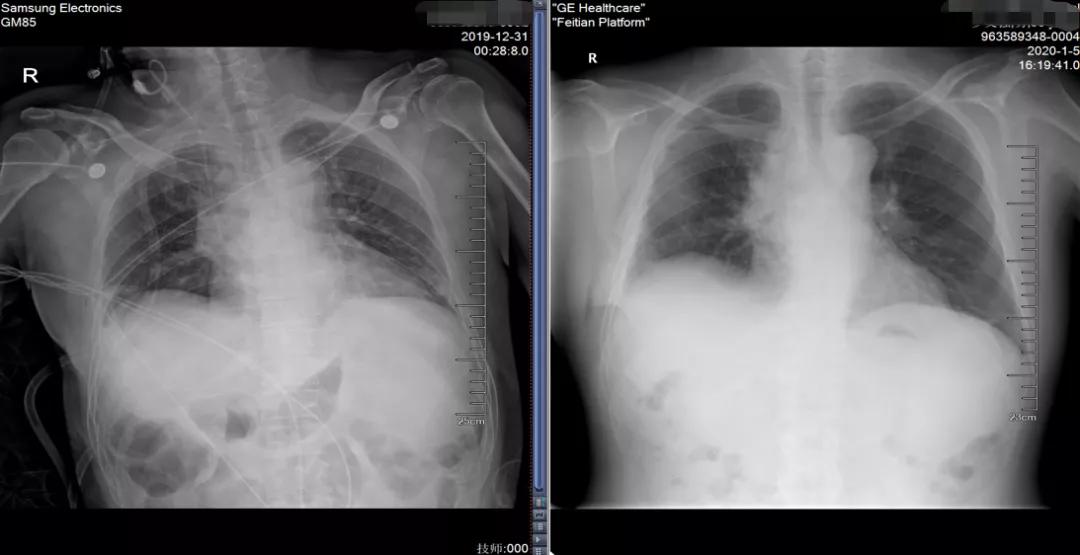

2019-12-31行全麻VATS单操作孔下右上肺叶切除+纵膈淋巴结清扫术

病理显示肿瘤完全消失

术后五天出院,恢复良好

术后随访

脑转移持续完全缓解

胸部无病灶复发/进展